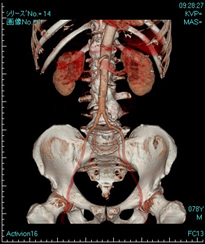

コンピュータ性能が大幅に向上したことにより、3D画像を作成することも可能です。このように種々の利点をもったこのCTは日々の診療に多大な貢献をしております。

肝臓造影CT動脈相 造影剤を使用することでより詳しく診断することができます。 3D-CT像 立体映像として観察できます。この画像では腹部大動脈から左右腎へと、左右総腸骨動脈への分岐が明確に観察できます。

3D-CT像 立体映像として観察できます。この画像では腹部大動脈から左右腎へと、左右総腸骨動脈への分岐が明確に観察できます。